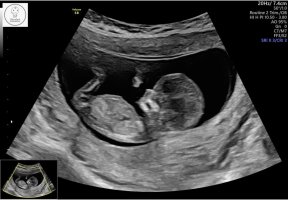

Så kjekt. Det fikk jeg også , herlig med film hvor armer og bein viser osv..9+3 idag, ble målt et par dager bak men ikke noe å bekymre seg over. Herlig å se mini armer og bein! Fikk video også, veldig gøy

Vis vedlegget 439629